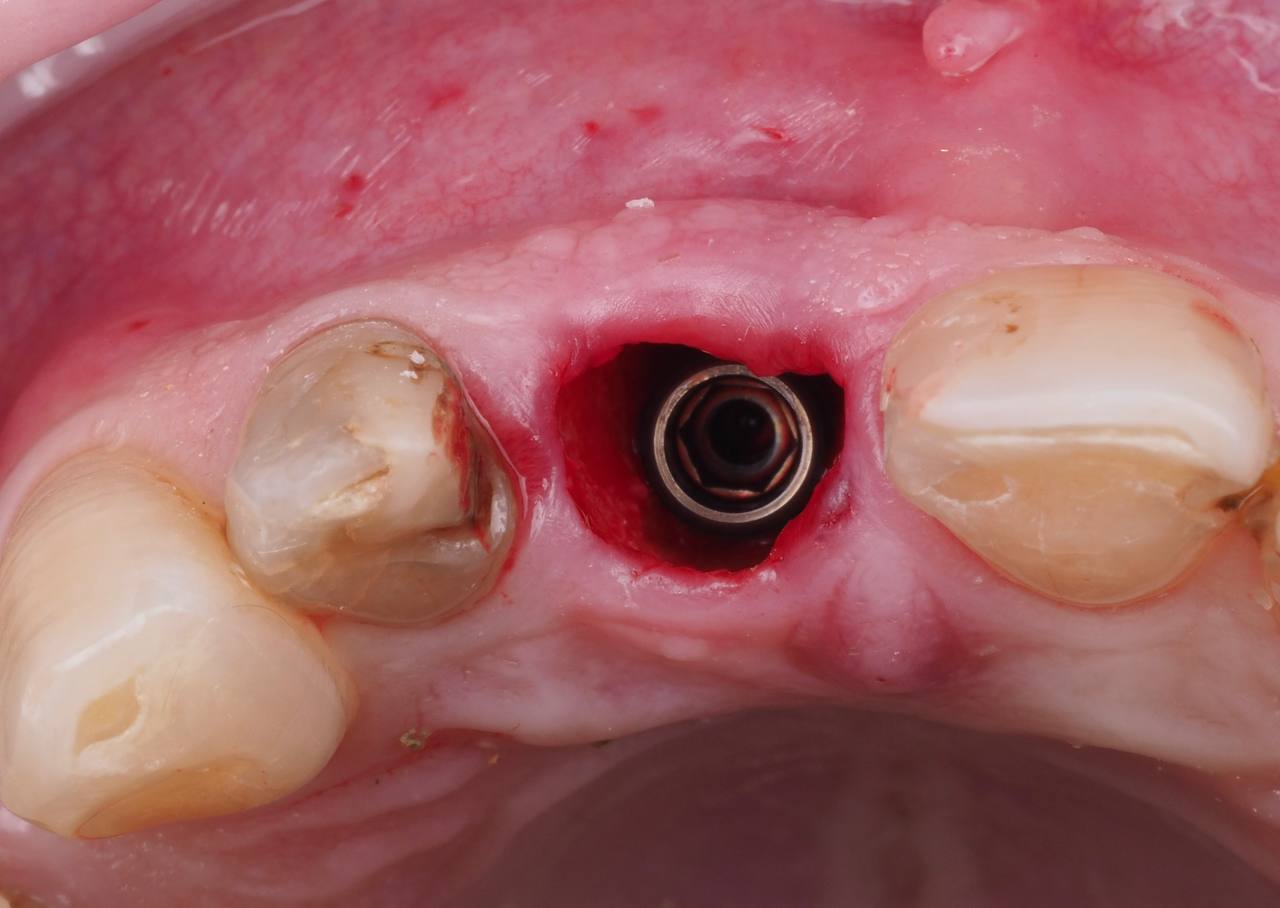

Одномоментная имплантация 1.1

AnyRidge, мультиюнит Octa, CCT, временная коронка